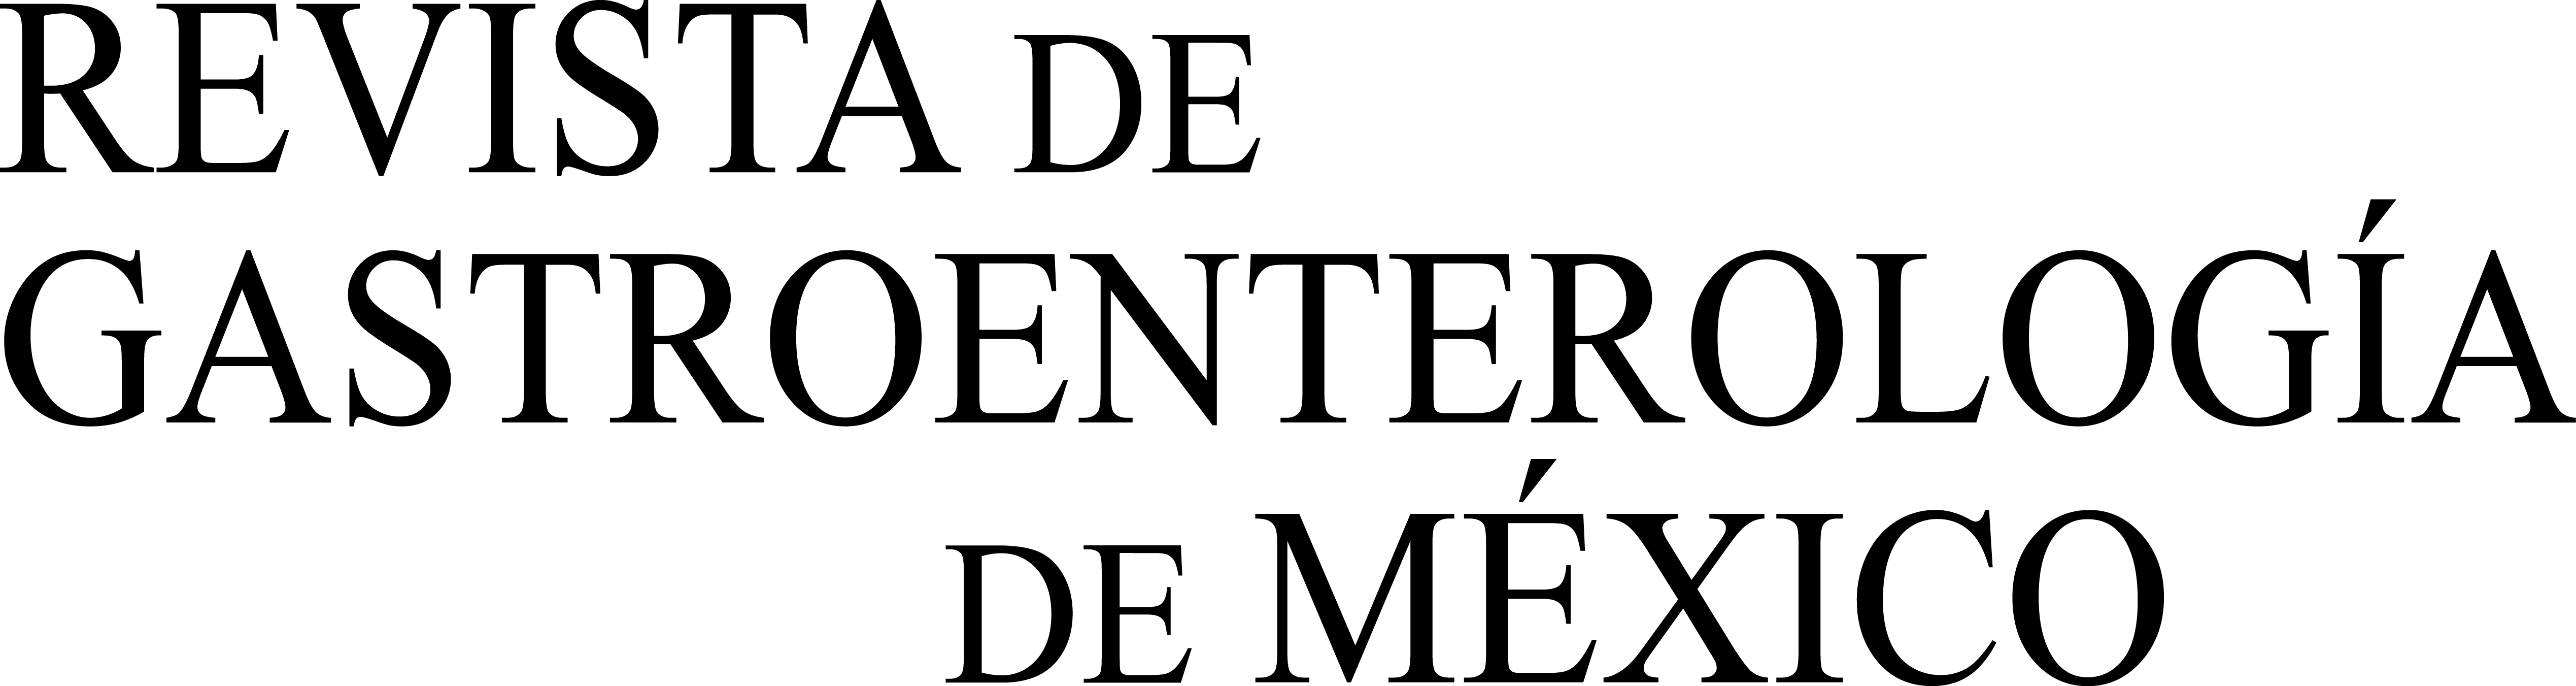

The first case was an 89-year-old woman with no family history of colon cancer. She presented with insidious clinical symptoms of 3-month progression that included anorexia, weight loss, and abdominal pain. Laboratory work-up results reported hypochromic anemia, leukocytosis with no neutrophilia, and elevated C-reactive protein. A computed tomography (CT) scan identified irregular thickening of the cecum, with infiltration of the pericecal fat and the terminal ileum wall, and no signs of obstruction, as well as numerous regional and retroperitoneal adenopathies (fig. 1A). Long colonoscopy detected an ulcerated and strictured mass that took up almost the entire cecal lumen and impeded the passage of the endoscope. Biopsies were positive for signet ring cell adenocarcinoma. Right oncologic hemicolectomy was performed and infiltration at the level of the right parietocolic peritoneum and the mesocolon was observed.

Anatomopathologic report: poorly differentiated adenocarcinoma of the colon with > 50% signet ring cell pattern (fig. 1B) with multiple tumor nodules and countless lymphatic embolisms, disperse tumor implants, and stage T4aN2bM1b (2010 ICC/AJCC TNM classification, 7th Edition). Immunohistochemistry showed microsatellite instability in the PMS-2 and MLH-1 genes. Adjuvant oncologic treatment was rejected.